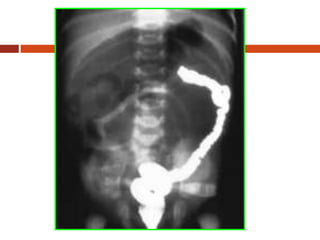

Imaging Studies

The diagnosis of the duodenal

atresia is confirmed on X-ray

examination. An abdominal

radiograph will show a dilated

stomach and duodenum,

giving the characteristic

appearance of a “double

bubble sign”

(the stomach and the proximal

duodenum are air filled), with

no gas beyond the duodenum

Duodenal atresia

Abdominal erect radiograph showing

distended stomach and duodenum with

a “double bubble” sign with no air

beyond the duodenum

In partial duodenal

obstruction, a plain film of the

abdomen will show a “double

bubble” appearance but there

is usually some air in the

distal intestine. Radiographic

findings in the annular

pancreas are usually

indistinguishable from

duodenal atresia and

stenosis.